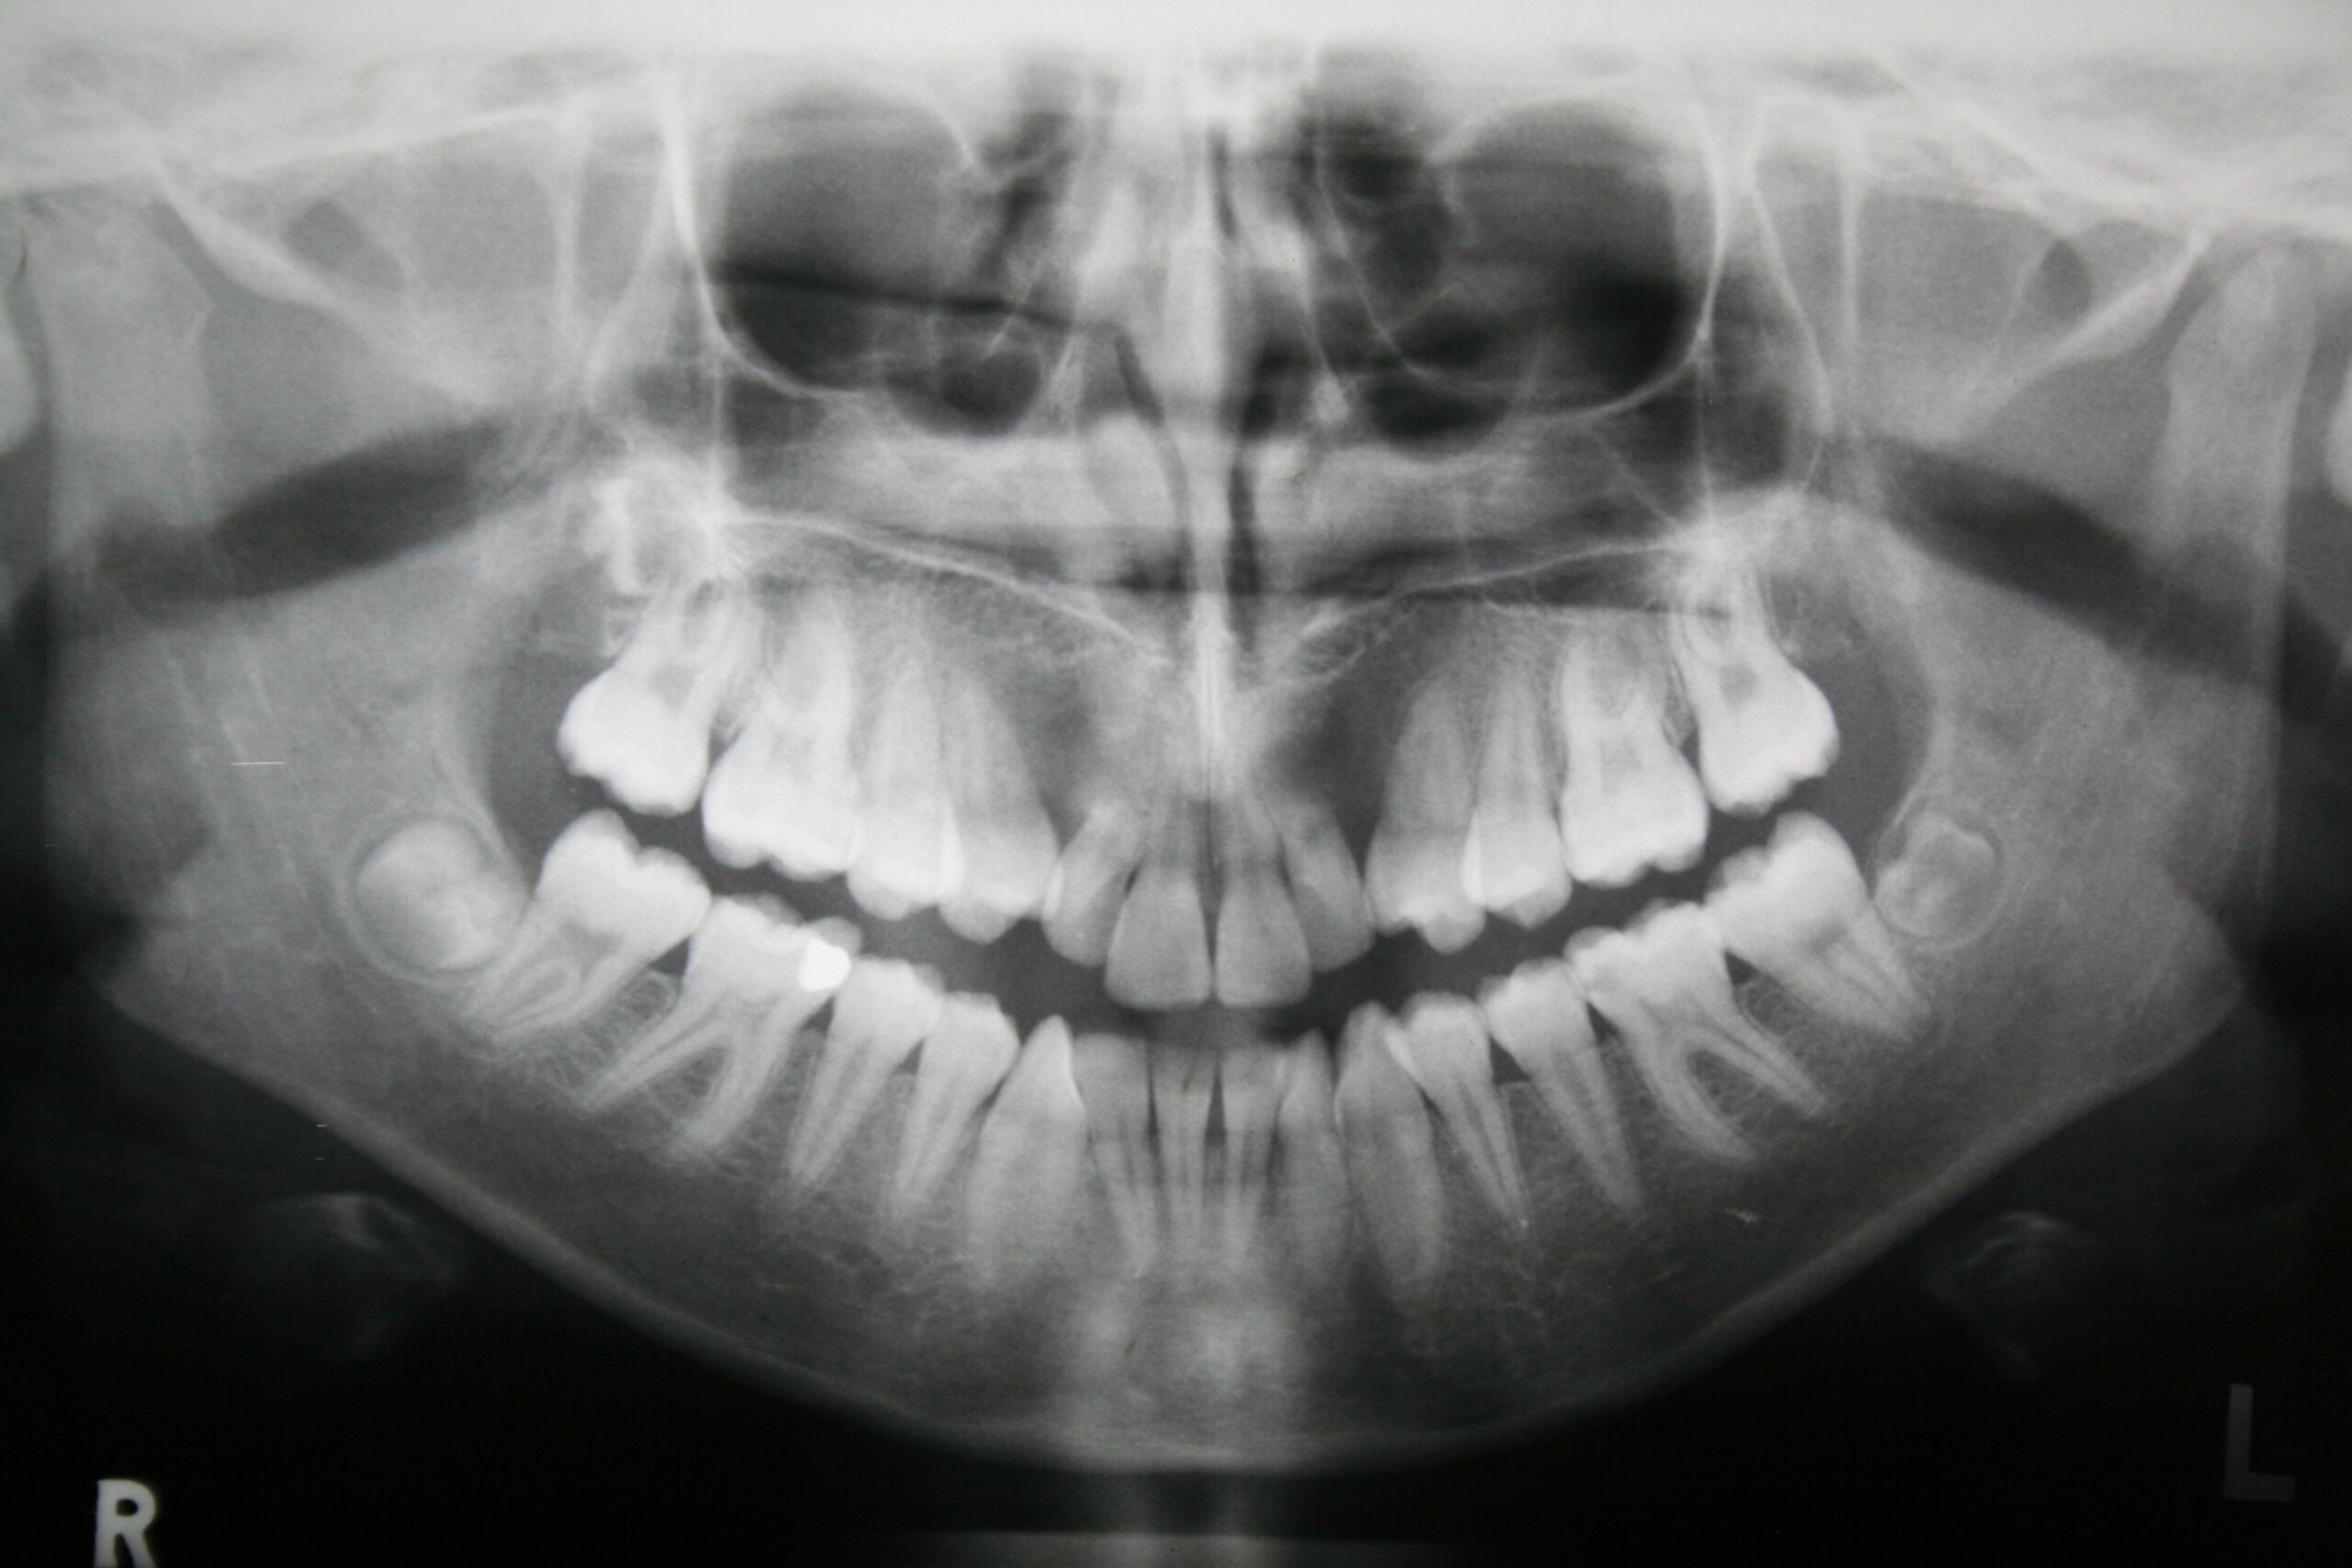

Broadly speaking, there are two different types of x-rays that you may need to get at the dentist. Let’s discuss them both now.

- Screening x-rays – Screening x-rays are done once per year as part of the routine preventive dentistry process. They’re called “screening” x-rays because they allow Dr. Landry to look for signs of common oral health issues, such as an infection below your gums, tooth decay, or a failing piece of dental work like a filling or crown.

- Diagnostic x-rays – Diagnostic x-rays are not used to look for oral health issues. Rather, they’re used to focus on a specific part of your mouth after an oral health problem is found, or after a specific procedure is recommended. They are only necessary if you have an oral health problem that needs to be addressed by the team at Consultants In Dental Aesthetics.

For example, if Dr. Landry notices that you have an infected tooth and it needs to be extracted, she may take diagnostic x-rays of the tooth to get a better view of the tooth and the location of the tooth in your mouth. Then, she can use this information to plan the extraction procedure and ensure the best possible results.

Digital x-rays are a very powerful diagnostic tool, since they allow Dr. Landry to look deeply into your gums, teeth, jaw bone, and other structures of your face, and identify problems that may not be diagnosable with a physical oral exam alone.